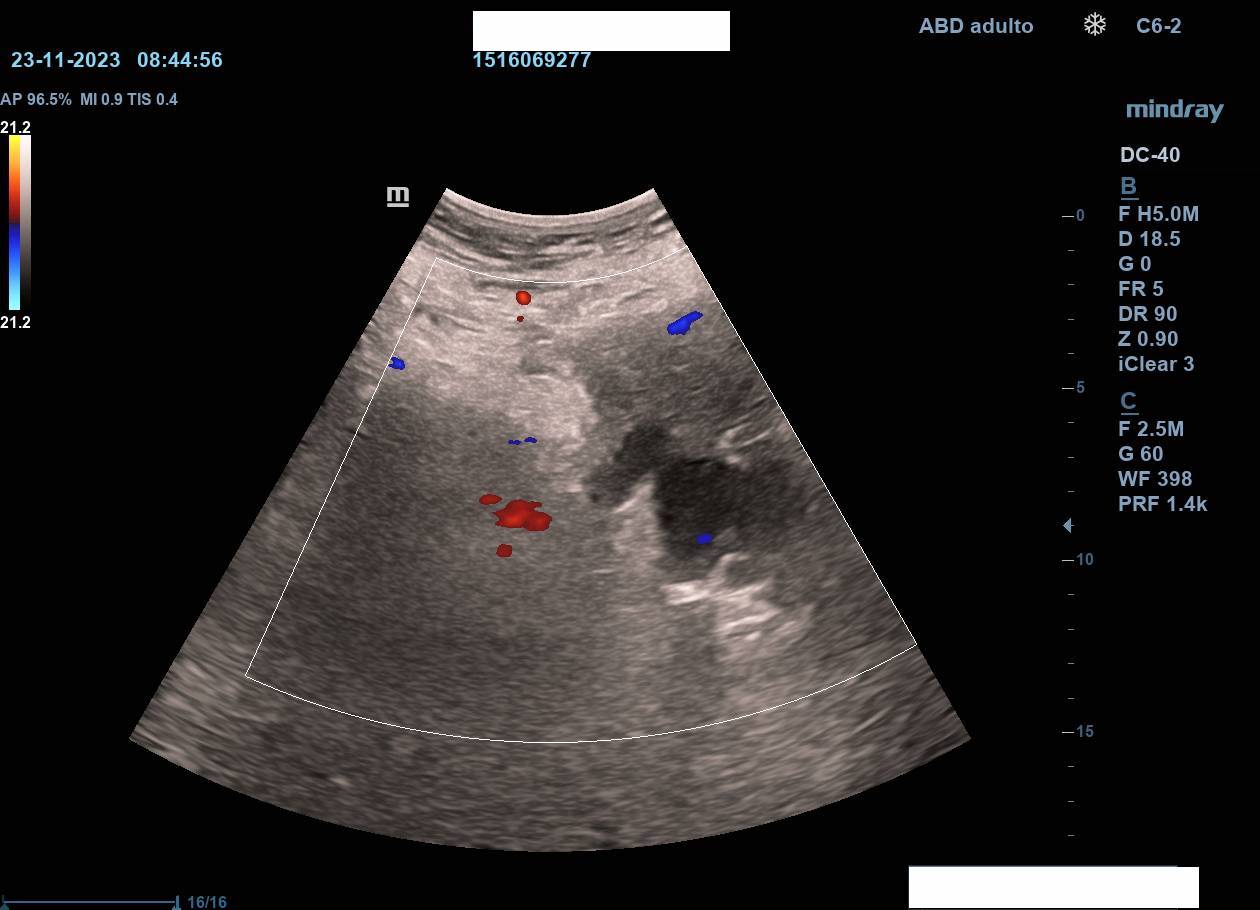

Hallazgos ecográficos

La ecografía en atención primaria permitió un abordaje inicial inmediato, objetivándose dilatación de asas intestinales en la zona de la tumoración, sospecha de ascitis y no visualización de riñón izquierdo (atrofia previa). Estos hallazgos, junto con la exploración, motivaron derivación urgente a Medicina Interna con sospecha de tumoración abdominal.